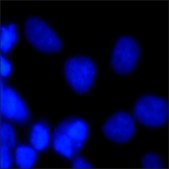

Bisbenzimide Hoechst 33342是双链高AT含量区域的特异染色剂,经证可替代几种已知的DNA嵌入剂。这种荧光染料已用于根据DNA含量分选活细胞选、流式细胞术DNA含量测定、活细胞染色质分布可视化。它已用于检测细胞BrdU掺入、细胞凋亡和细胞周期分配的初始阶段研究,。正在分裂或复制的染色体不会被这种染料染色。

适用于DNA,染色体和细胞核染色。可用于荧光显微镜或流式细胞术。